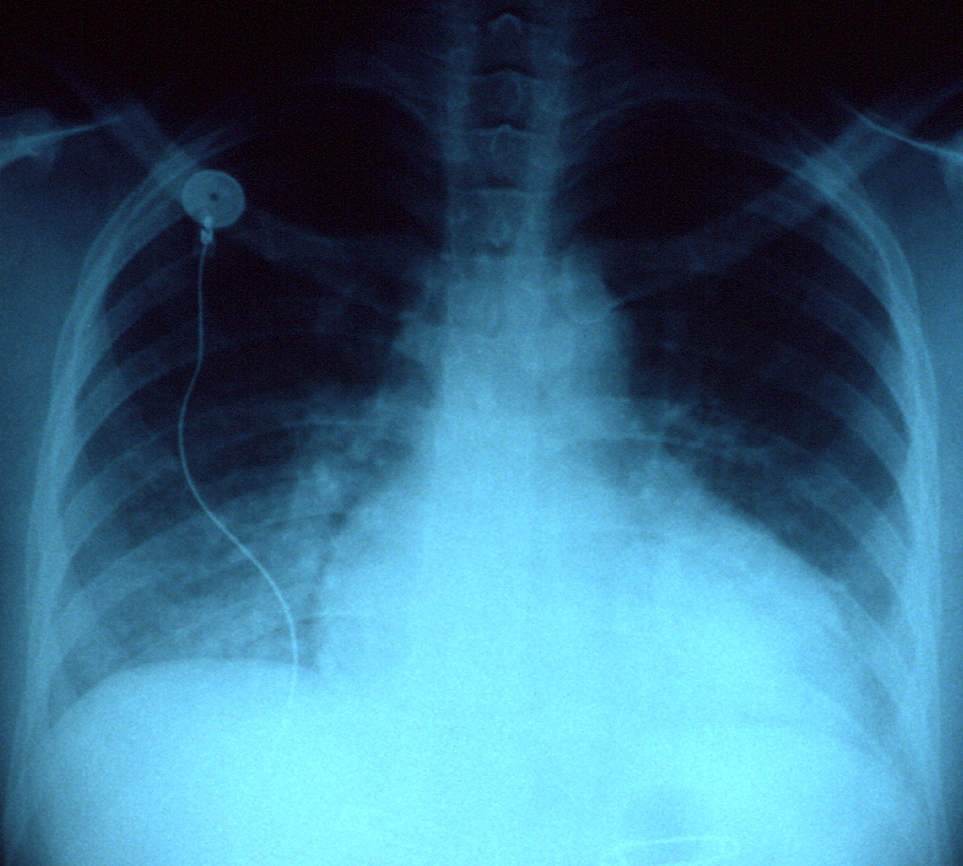

- Pulmonary Edema

- Pulmonary congestion (wheezing and abnormal sputum cytology)

Congestion in lungs